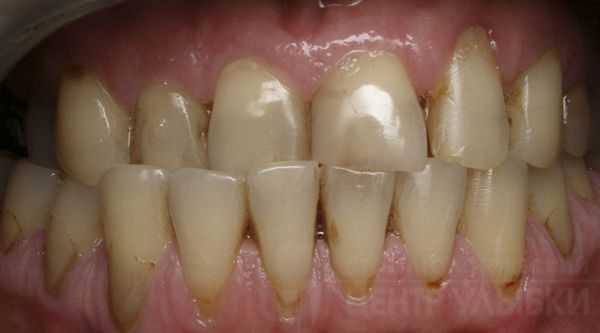

Глубокое резцовое перекрытие, сужение обоих зубных рядов, ротация и девиация нижней челюсти, смещение центральной линии

Начальная степень глубокого прикуса выражается образованием небольших эстетических дефектов передних зубов - трещинки, мелкие сколы эмали.

Глубокий прикус средней тяжести - интенсивное стирание эмали на внутренней стороне верхних зубов и на внешней стороне зубов нижней челюсти.